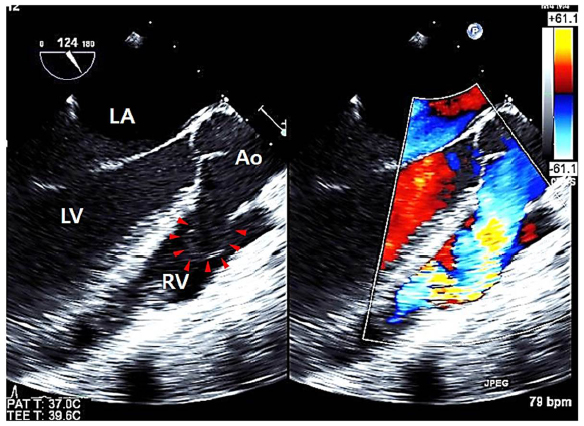

Figure 4: Transesophageal echocardiography.

Transesophageal echocardiography shows a protruding aneurysmal sac (red arrow heads) with shunting from the right coronary sinus to the right ventricle.

LA: left atrium; LV, left ventricle; Ao, aorta; RV, right ventricle.